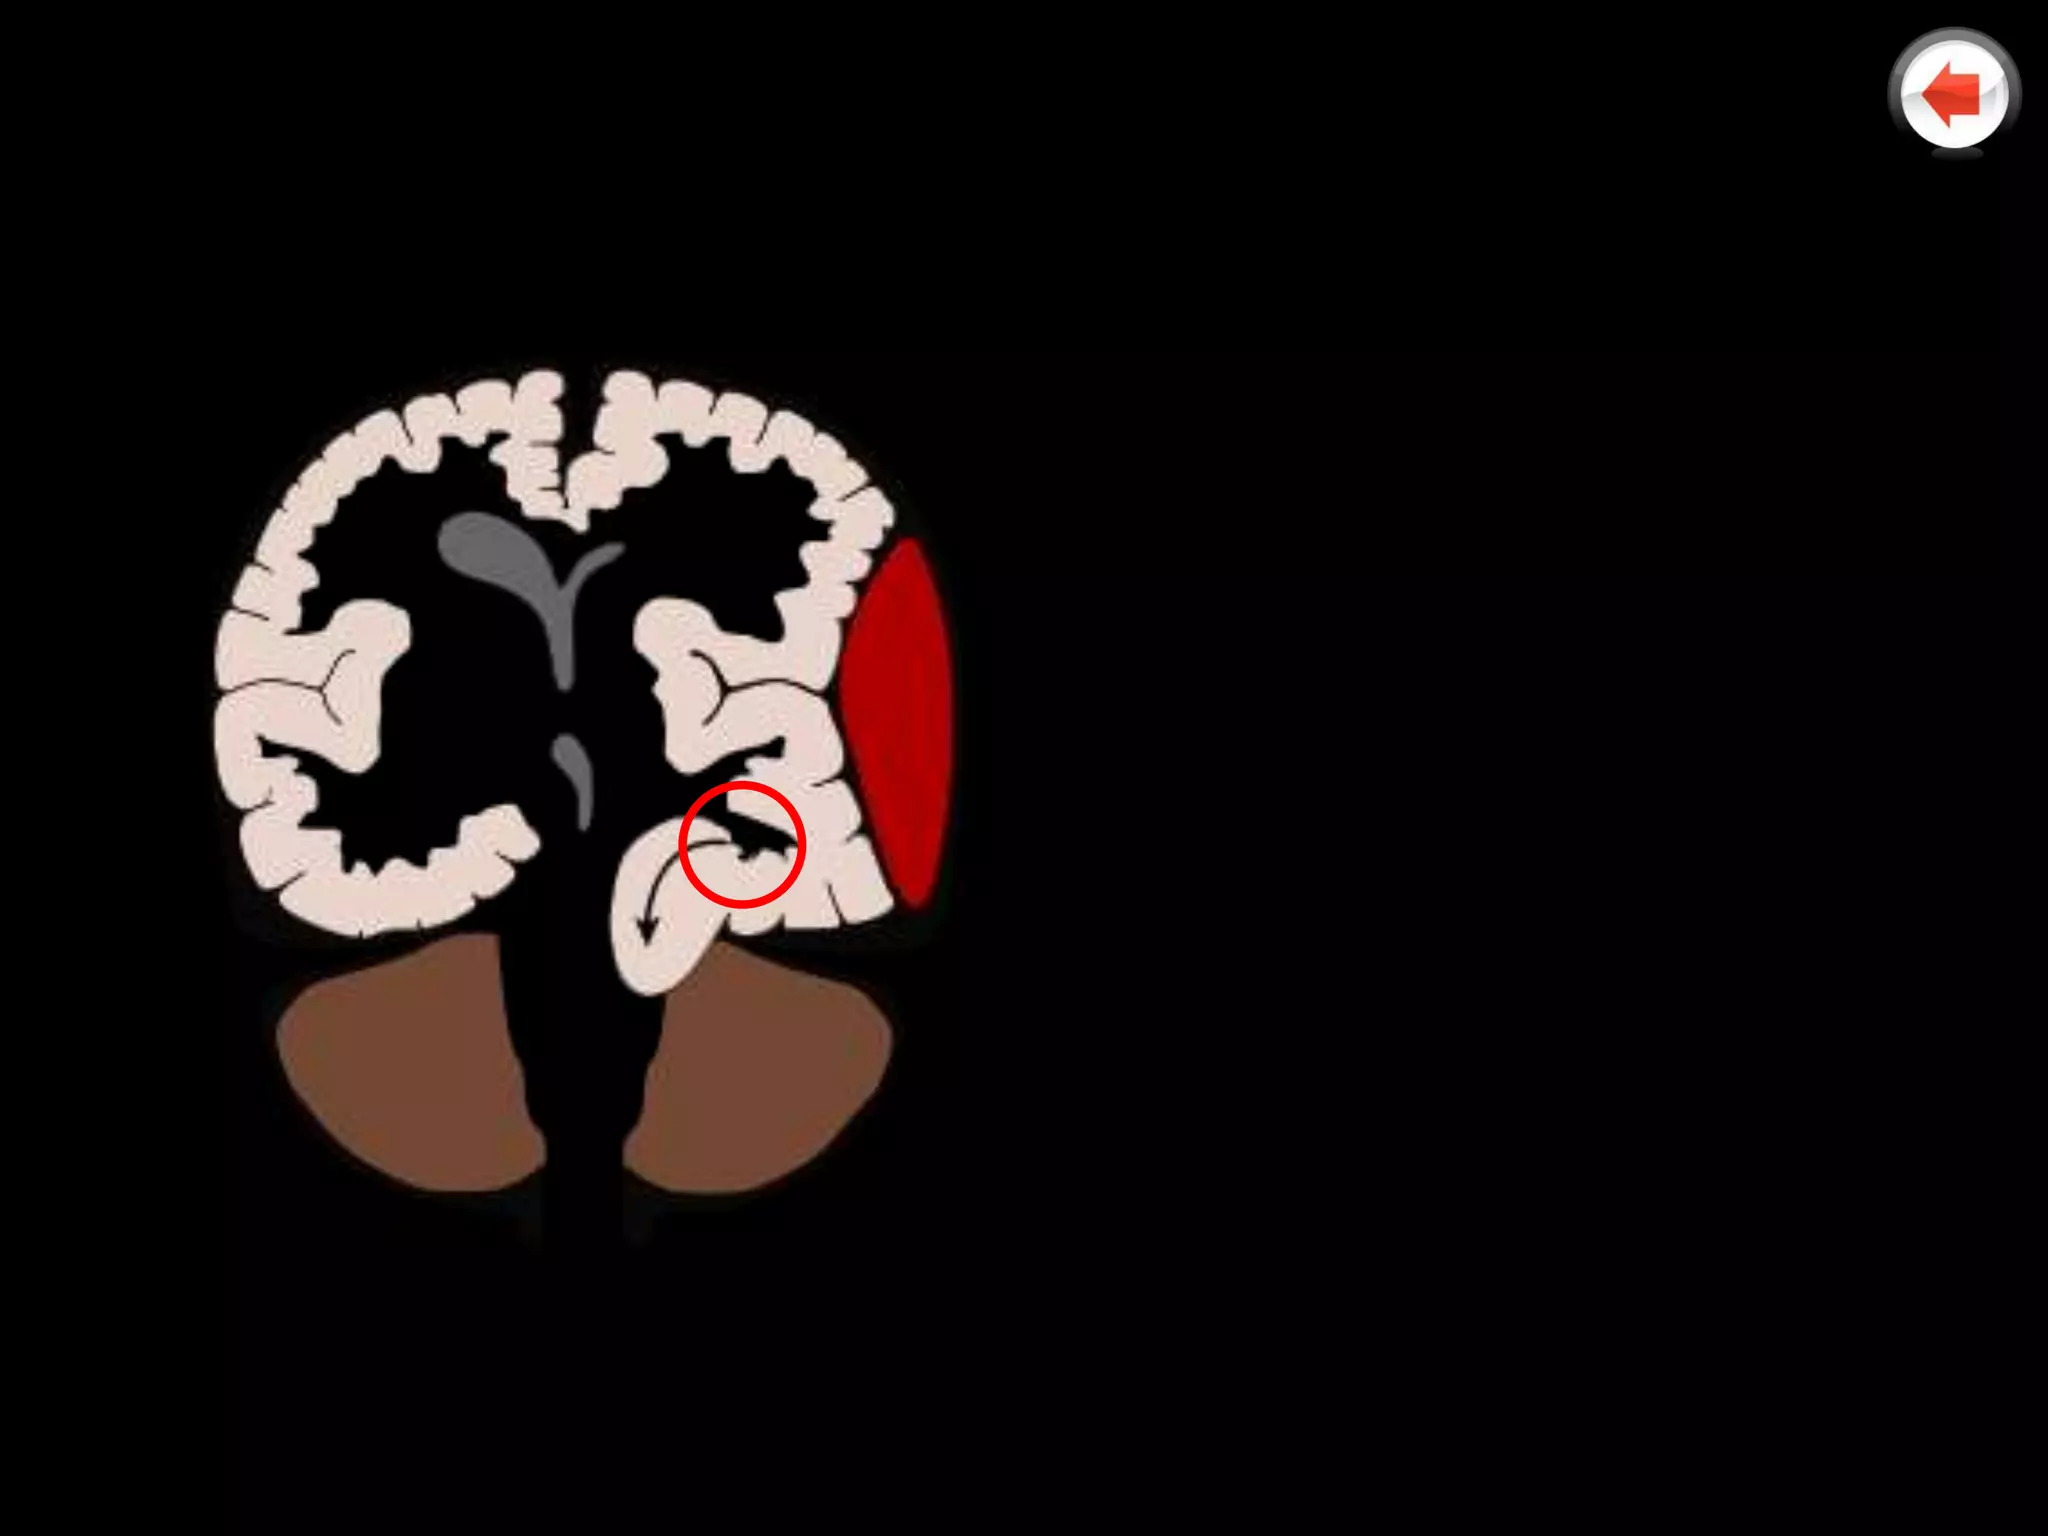

   Notice how the

falx is deviated

(white arrow)

due to a space

filling lesion

(red outline)